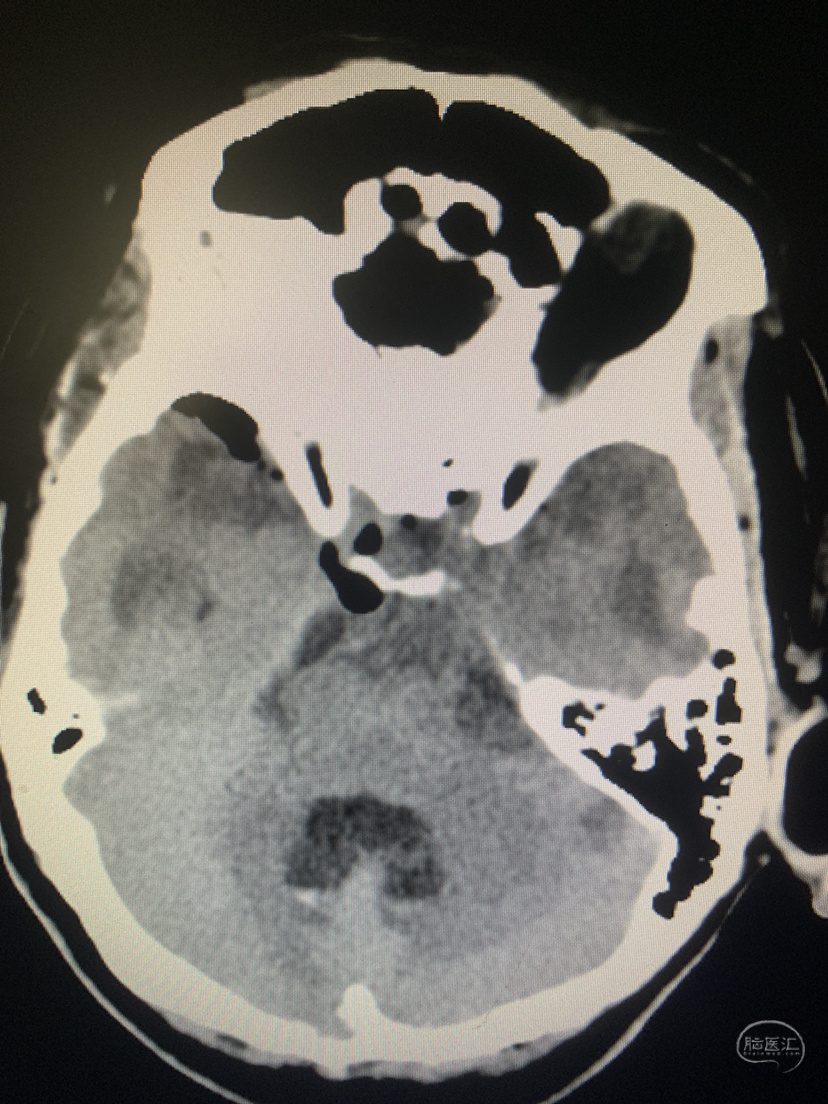

术前术后对比

术后CT